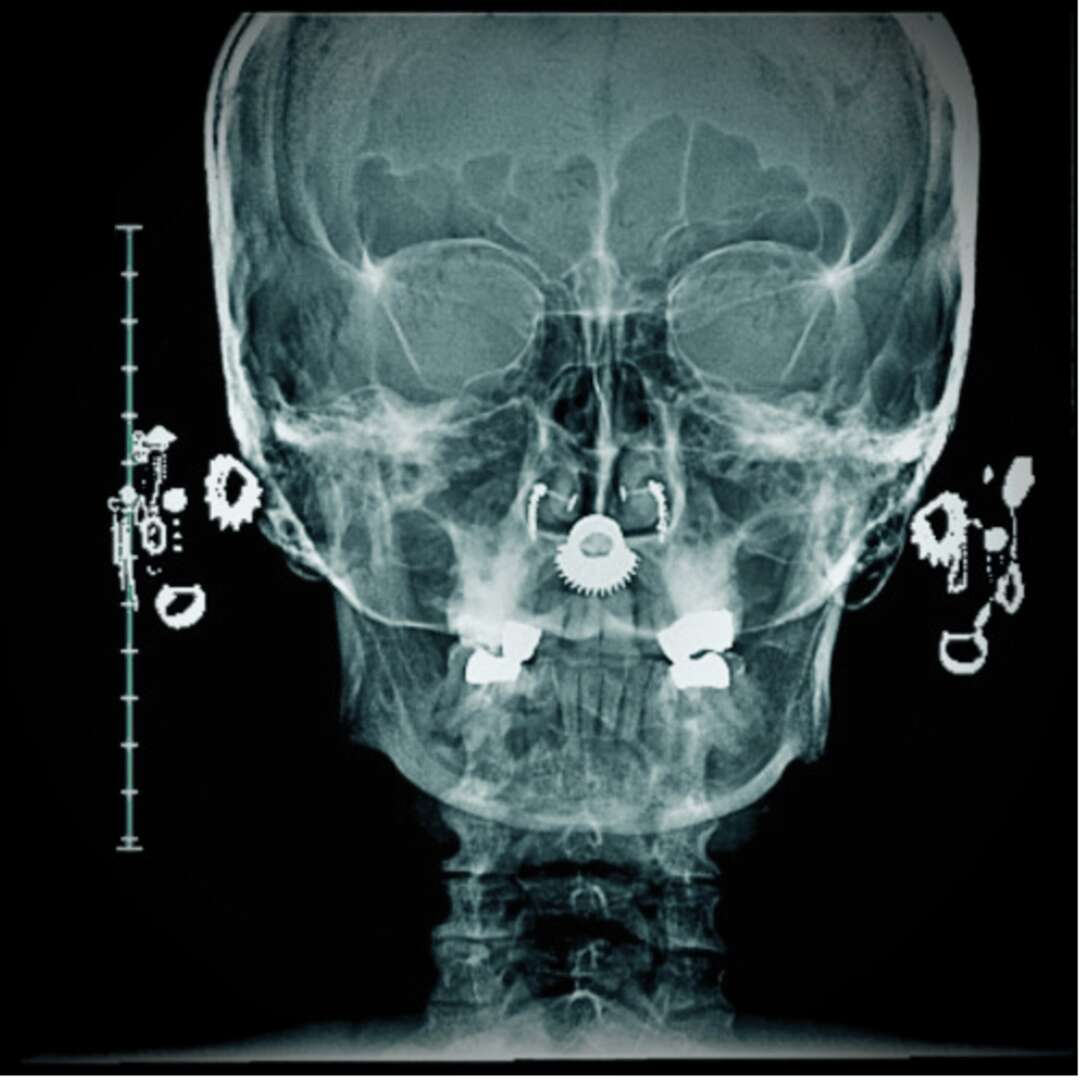

I have been living with fibromyalgia for most of my life and often get told that I look fine what’s the problem, when I have to sit out a song or stop and take a break from molding a song. Usually when I explain that I have fibromyalgia, I get a blank stare or told that it is a lazy made up woman’s disease. Depending on the person’s reaction will determine if I continue to collaborate further with the self anointed internet doctor. There are days that I can not play music because of the intense pain and fatigue that usually comes with a side of tension headaches or migraines that make me lose sight. I can’t play live anymore because I never know what horrors await me everyday. I also sing in a death metal band and I am slowly unable to continue to do this because of the exhaustion that comes with it. Luckily in death metal, vocals can be slurred or unrecognizable so I can roll with the punches on certain parts and at least sound sort of the same as if I was having a good day. I feel like my own body has betrayed me. This is an invisible disease that many folks do not understand even doctors.

When I used to go to concerts and see all my favorite song writers, I would hope they would sing that one song that cuts like a knife and they would and I would see the pain in their eyes and not understand that they were in a way, in that moment, feeling all those feelings over and over each night they did these sad songs. After I started writing music and performing, I felt the heaviness and horrors pool into my thoughts. I then would see these songs in a different light and saw them as being re-traumized. I was also deep into trying to find out why I was so tired and having insane muscle pains like electric shocks pulse through my body. So it was an all around painful experience.